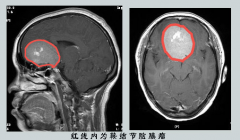

左眼失明后右眼视力也下降 检查发现是脑膜瘤

人到一定年纪后,眼白会浑浊,相应的视力会日益下降。若是视力短期内下降,有可能是正常的老年人视力反应。若是短期内下降厉害甚至还有失明的风险,那就需要警惕,这有可能...